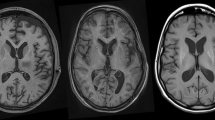

Concordance of asymmetric imaging abnormalities with symptom dominant sides

Representative 18F-THK5351 PET images are provided in Fig. 1. All CBS patients exhibited asymmetric THK5351 uptake in the cerebral cortex and subcortical white matter, aligning with their symptoms. Asymmetric uptake was also observed in the striatum, corresponding to the laterality of symptoms in all patients (Supplementary Fig. 1). The concordance of the laterality of imaging abnormalities (contralateral to the symptom-dominant side) was 100% for THK5351 PET in both the cerebral cortex/subcortical white matter and striatum, 86.7% for brain structural MRI, 81.8% for brain perfusion SPECT, and 90% for DAT SPECT (Fig. 2).

Representative 18F-THK5351 PET image results overlayed on structural brain MRI images. (A–D) Average results of seven healthy control volunteers. Physiological tracer uptake was primarily observed in the bilateral striatum, thalamus, and amygdala, where MAO-B is abundant. (E–H) Results for a 69-year-old man with possible CBS and a disease duration of one year (Case 6). The patient exhibited ideomotor apraxia, right dominant limb kinetic apraxia, rigidity, dystonia, and myoclonus. CSF biomarkers indicated non-AD. Left-dominated tracer uptake was observed in the frontal and parietal lobes, including the precentral gyrus. (I–L) Results for a 70-year-old man with probable CBS and a disease duration of 4 years (Case 3). The patient showed right-dominant limb kinetic apraxia, cortical sensory deficits, mild dysarthria, limb dystonia, and limb myoclonus. Left-dominated tracer uptake was observed in the frontal and parietal lobes, including the precentral and postcentral gyri. (M–P) Results of a 71-year-old man with possible CBS and a disease duration of a year (Case 4). The patient showed left-dominant limb kinetic apraxia and limb rigidity. CSF biomarkers suggestive of AD. Right-dominated tracer uptake was observed in the frontal, parietal, and temporal lobes. (E–P) Tracer uptake was observed in both the cerebral cortex and associated white matter. Striatal tracer uptake was higher contralateral to the symptom-dominant side in all patients. Color scales represent the uptake ratio index (URI), with the cerebellum as the reference region.